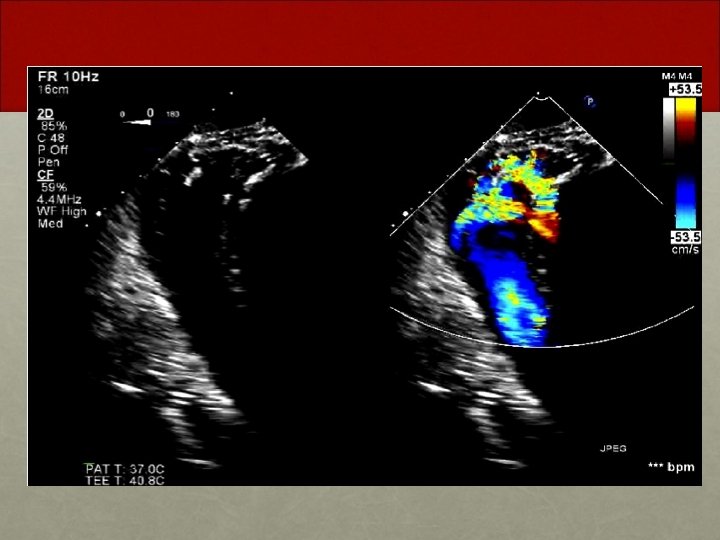

Follow Up One month later • Patient found to have residual VSD despite VSD patch repair post-infarct • Patient brought to the cardiac catheterization suite for possible percutaneous VSD closure

Significant Residual shunt